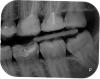

Ksenia Nikitishna Опубликовано 30 июля, 2013 Поделиться Опубликовано 30 июля, 2013 Здравствуйте,посоветуйте, пожалуйста, какие зубы нуждаются в лечении/удалении.возраст пациентки 29 лет. Собираюсь беременеть, когда лучше начать лечение: до или после беременности? Заранее спасибо. Ссылка на комментарий

juli63 Опубликовано 30 июля, 2013 Поделиться Опубликовано 30 июля, 2013 Здравствуйте! Лечить до беременности!Необходима профгигиена полости рта, 47 зуб на удаление, 26,27,46 эндодонтическое лечение, лечение 36,37,28,25,16,14,15. Конкретика только после осмотра полости рта, т.к. для однозначной оценки- данных мало. Ссылка на комментарий

IvanK Опубликовано 30 июля, 2013 Поделиться Опубликовано 30 июля, 2013 Здравствуйте,Проф.гигиена + обучение гигиенеУдаление 46,47 с последующей имплантациейПерелечивание 26,27 с последующим протезированием коронками Лечить до беременности Ссылка на комментарий

juli63 Опубликовано 31 июля, 2013 Поделиться Опубликовано 31 июля, 2013 Juli63, спасибо! а вы не подскажете, судя по снимку, под 26 и 27 есть инфекция? на сколько возможно лечение 46-го без удаления? на Ваш взгляд.Да на здоровье! Скорее да чем нет в 27, в 26 вижу проблему в щечной системе корней, не могу ответить на 100%, т.к. ОПТГ не отражает действительность в полной мере. Для конкретики (в идеале) я бы сделала прицельные снимки и КТ. По поводу 46- как эндодонтист, предпочитаю сначала увидеться с зубом глаза в глаза , прежде чем отправить его на удаление, т.к. ОПТГ и прицельные снимки дают 2D формат и возможно искажают реальное положение вещей. Но, хочу подчеркнуть, всегда советуюсь с ортопедом и хирургом, с целью определения прогноза лечения и его целесообразности. P.S.: В медицине не бывает 100%. Есть прогноз. Ссылка на комментарий

juli63 Опубликовано 31 июля, 2013 Поделиться Опубликовано 31 июля, 2013 подскажите, пожалуйста, целесообразно ли ставить мост после удаления 46 и 47? Нет, т.к. расстояние между 48 и 45 слишком большое. В этом случае необходима имплантация. 1 Ссылка на комментарий